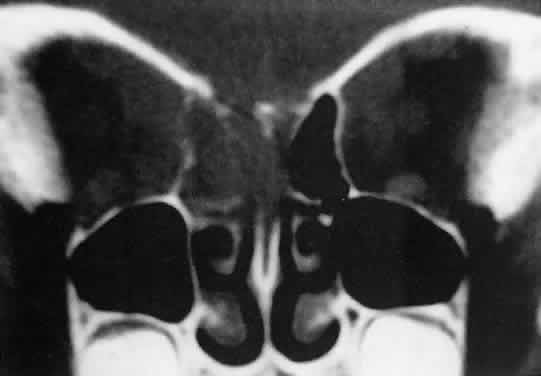

Orbital myositis may represent a greater proportion of cases of IIPT in childhood than in adulthood, and involvement of multiple extraocular muscles may occur more frequently in children than inadults. In orbital myositis, early diplopia and increased discomfort with attempted eye movement are typical symptoms. CT may show enlargement of one or more extraocular muscles in one or both orbits (Figs. 21 and 22). When a single muscle is involved, the specter of a primary or metastatic neoplasm within the muscle may be raised. However, external inflammatory signs, considerable pain and limited motility, and an explosive onset of symptoms within 24 hours all suggest orbital myositis. The uniform enlargement of the muscle, including its tendinous insertion (see Fig. 22), also helps distinguish the process from a neoplasm, which might be expected to produce a more focal, globular expansion. Echography may support the diagnosis of inflammation by showing edema in the episcleral space as a relative sonolucency between the scleral and orbital fat echoes (Fig. 23). Its CT counterpart is an increase in the radiodensity and thickness of the ocular tunica.

Fig. 21. A. This 16-year-old boy had acute onset of bilateral proptosis, pain, diplopia, chemosis, and conjunctival injection. B. Bilateral enlargement of the superior and medial rectus and inferior oblique muscles. Other sections showed similar involvement of other extraocular muscles.

Fig. 22. The uniform enlargement of the left medial rectus muscle, including its tendinous insertion, is characteristic of orbital myositis.